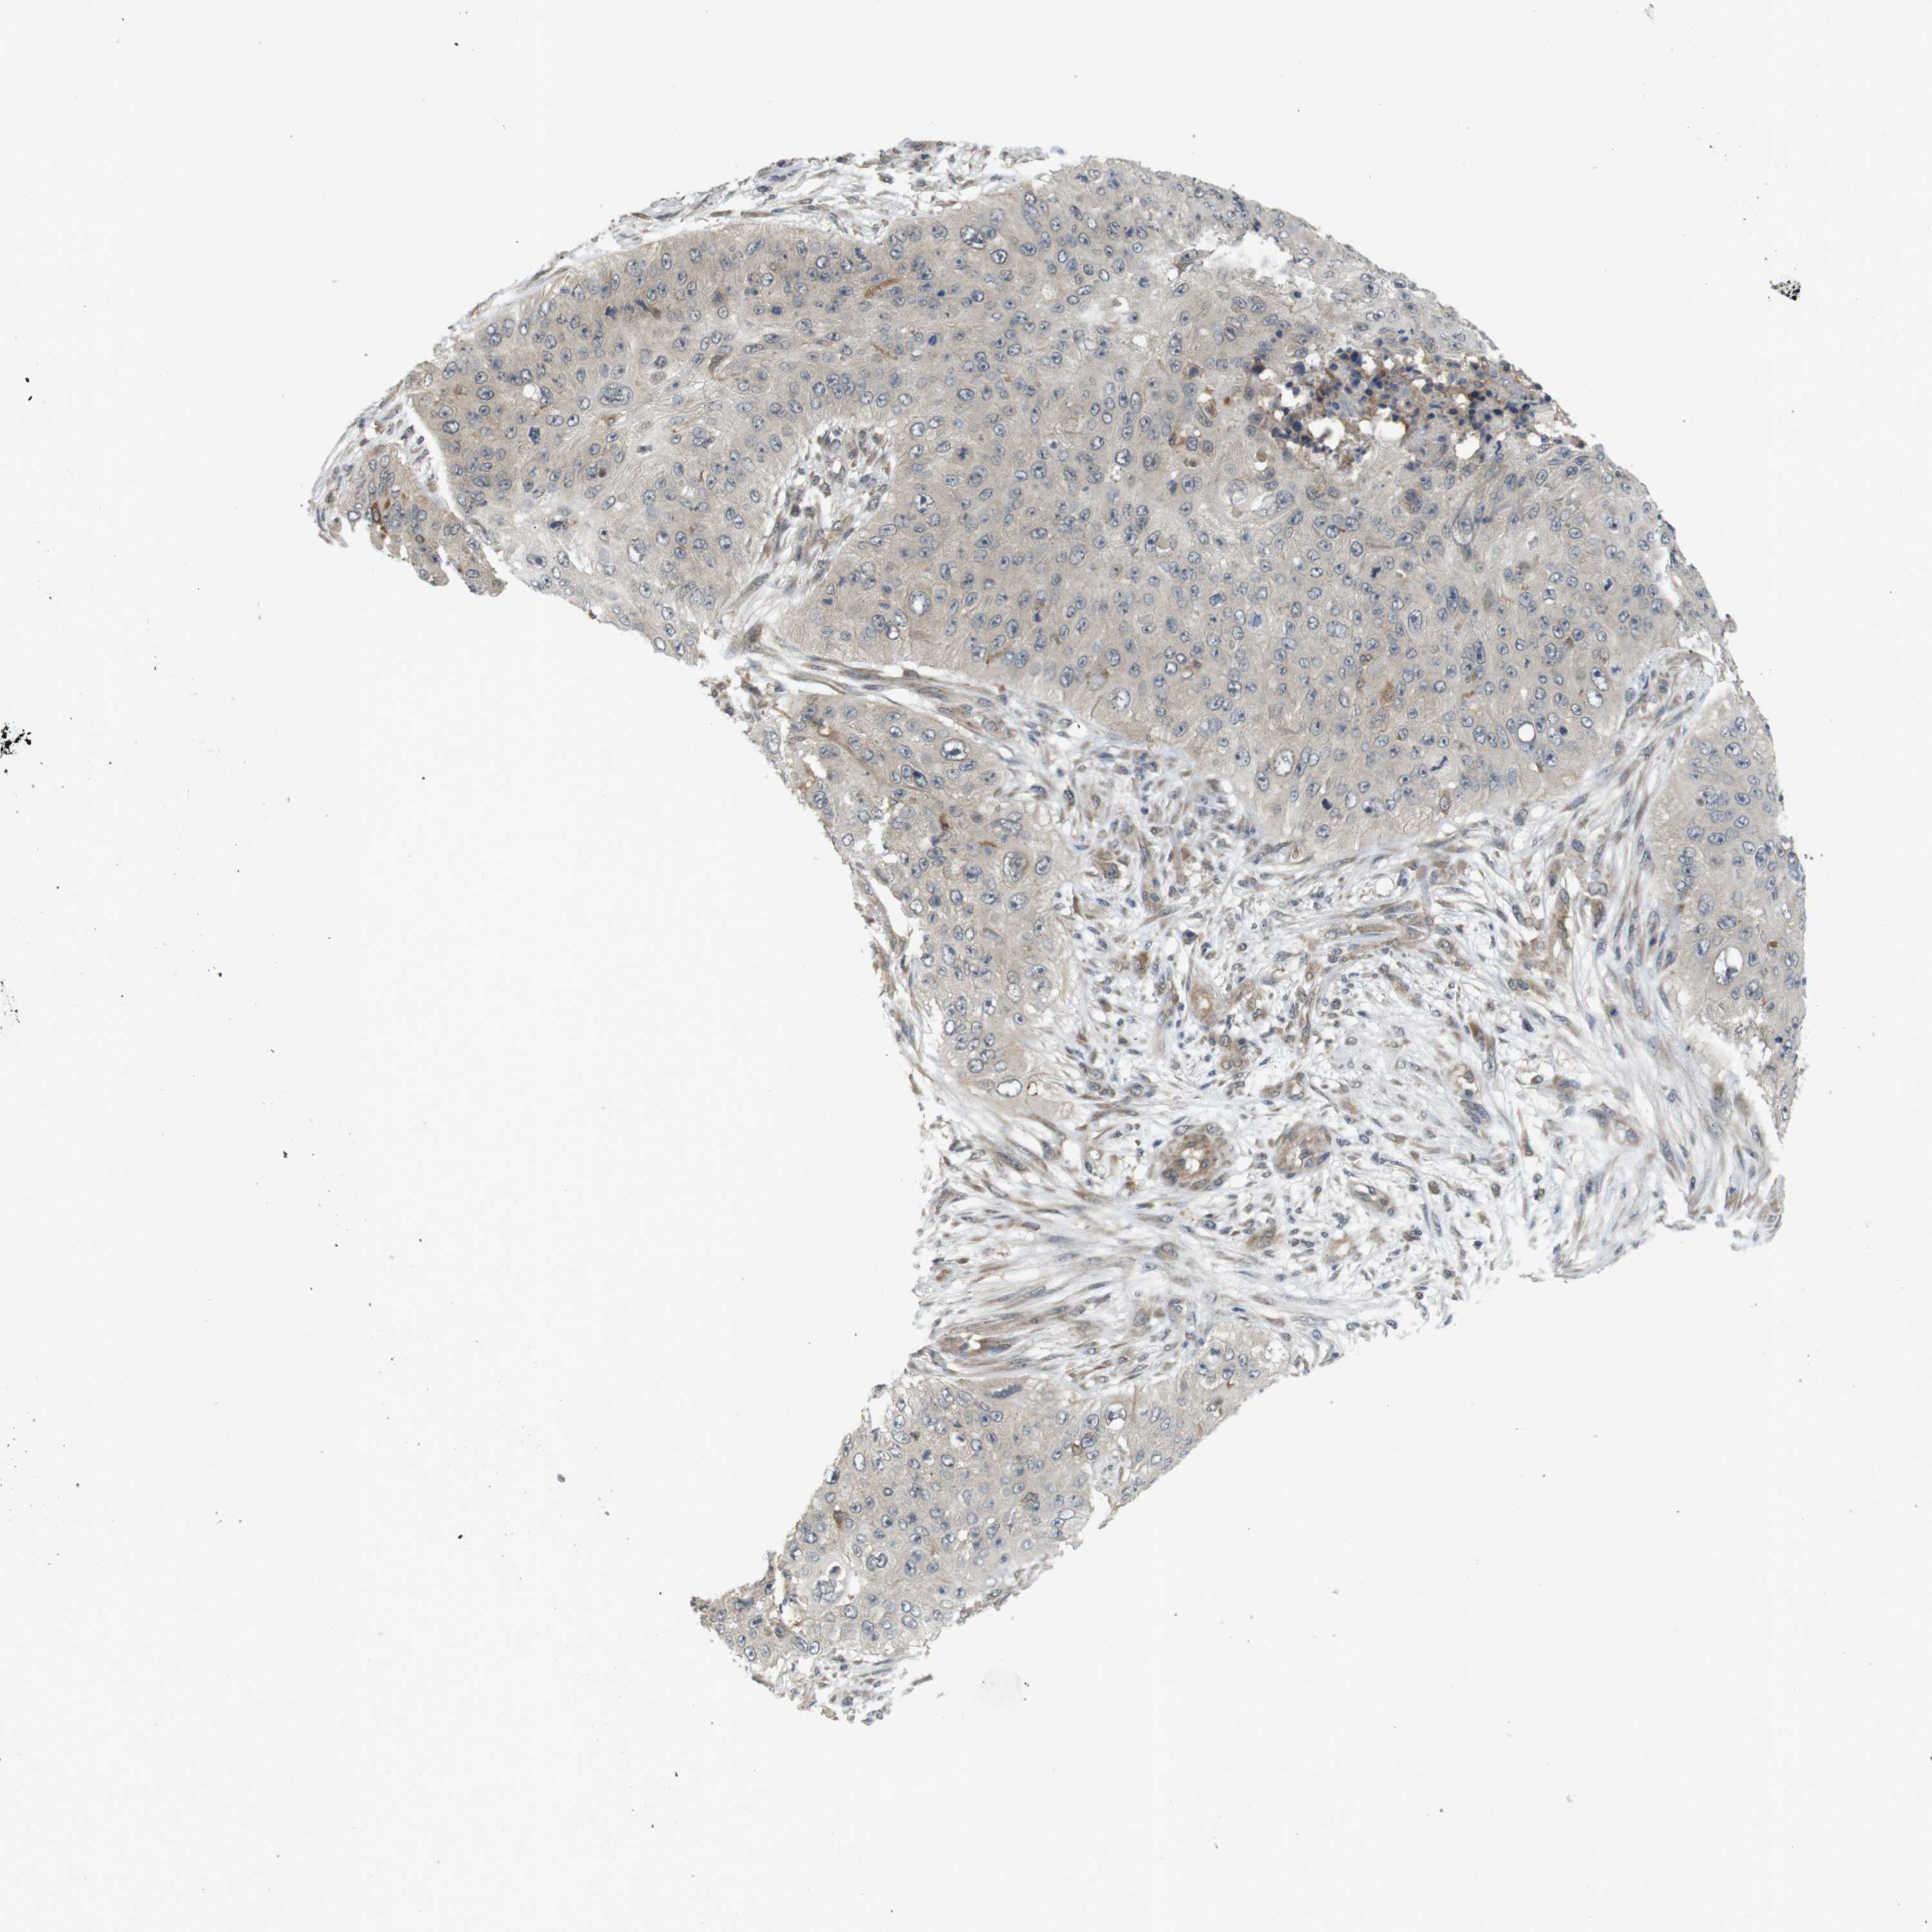

SKIN CANCER

Basal cell and squamous cell cancer